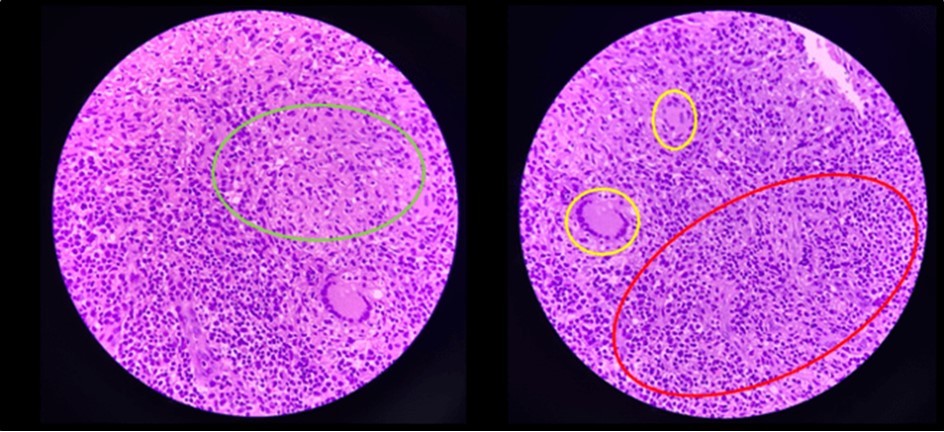

Biopsy showed chronic granulomatous inflammation with caseation necrosis and Langhan’s type giant cells consistent with tuberculous etiology (Figure 6, and Figure 7). TB PCR detected Mycobacterium tuberculosis, Rifampicin (MTB, RIF) resistance indeterminate. Category I Anti-TB treatment for six months was started and the service planned to repeat both colonoscopy and CT-scan after the initial round of anti-TB treatment. Currently, the patient is able to work with no abdominal pain and was able to tolerate her anti-TB drug regimen

Figure 7.Pathologic slide in the high power field. Inside the green circle is the epitheloid histiocytes. The yellow circles are the Langhan’s type multinucleated gian cells. And inside the red circle is the lymphocytic infiltrates. Which is suggestive of tuberculous etiology.